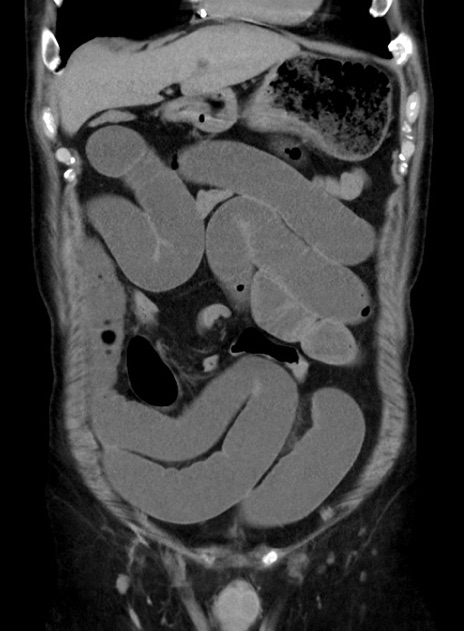

症例38(冠状断像)

【症例】70歳代 男性

【主訴】腹痛・嘔吐

【現病歴】昨晩より、嘔吐・腹痛あり。今朝になっても嘔吐あり。来院。

【既往歴】心臓バイパス手術、開腹胆摘、腸閉塞

【身体所見】BP 107/71mmHg、HR 116/min、腹部:平坦、軟、下腹部に軽度圧痛あり。反跳痛なし。

【データ】WBC 15100、CRP 0.32